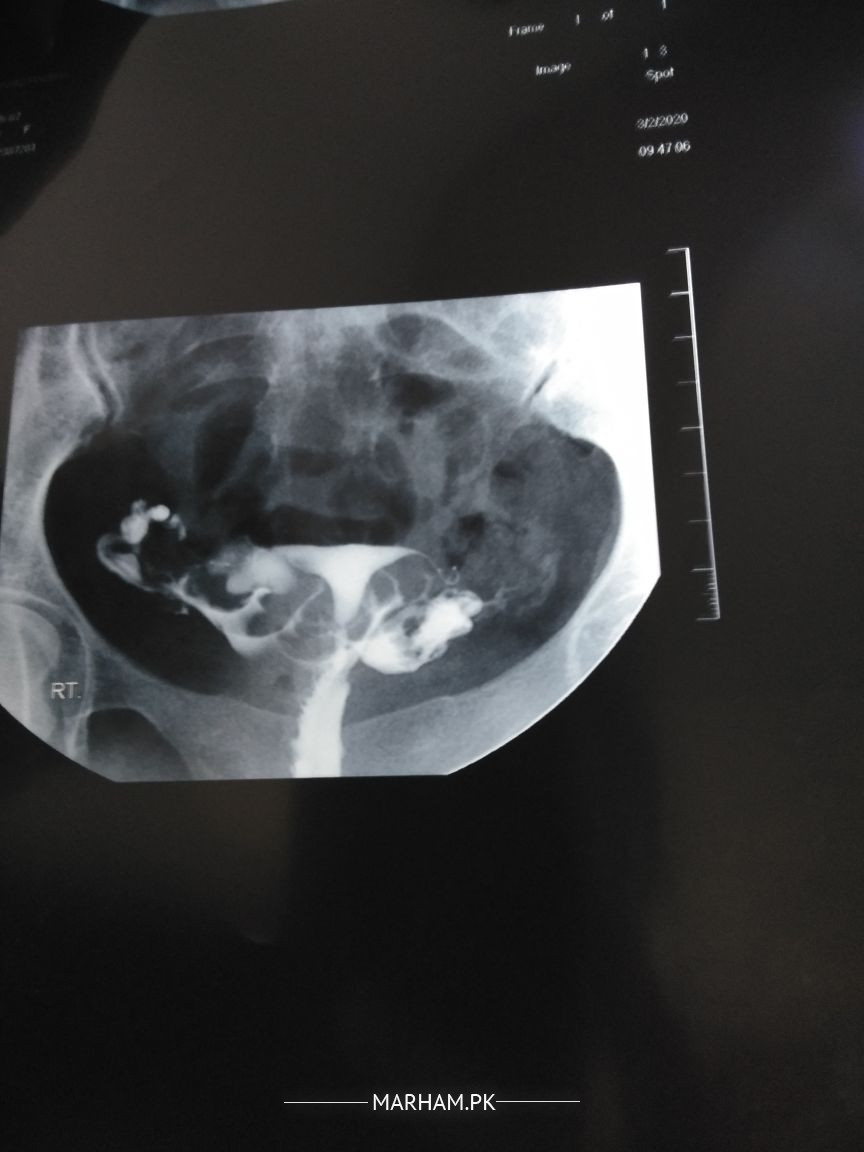

Hi, I got my HSG done last year. The report says that both the fallopian tubes are patent. I visited many doctors since then and all considered the report valid (none checked the film). However, on the basis of the report, my doctor has scheduled an IUI round this month. Recently, I met a doctor who checked the film and said that it seems that the tubes are not patent and laparoscopy should be done to check for it. Now the problem is if the tubes are not patent, there is no point of even getting an IUI. I am attaching the report as well as the films. Want an opinion on either I should start taking my ovulation induction pills and continue with the IUI procedure or not take my ovulation induction medicines and wait to see my doctor (the appointment is scheduled next week).

on both side spilled dye can b seen... its normal hsg. still if you want to take second opinion then report can be checked by sime radiologist... yahan tak bat laparoscopy ki hai it us best to diagnose so many problems responsible for not conceived till now.. including tubal patency

spill is seen on both sides.

U tubes r patent.

Eens to have some old infection causing ur tubes beaded in appearance

IUI will fail

Please take opinion from expert radiologist. At least one tube is patent.